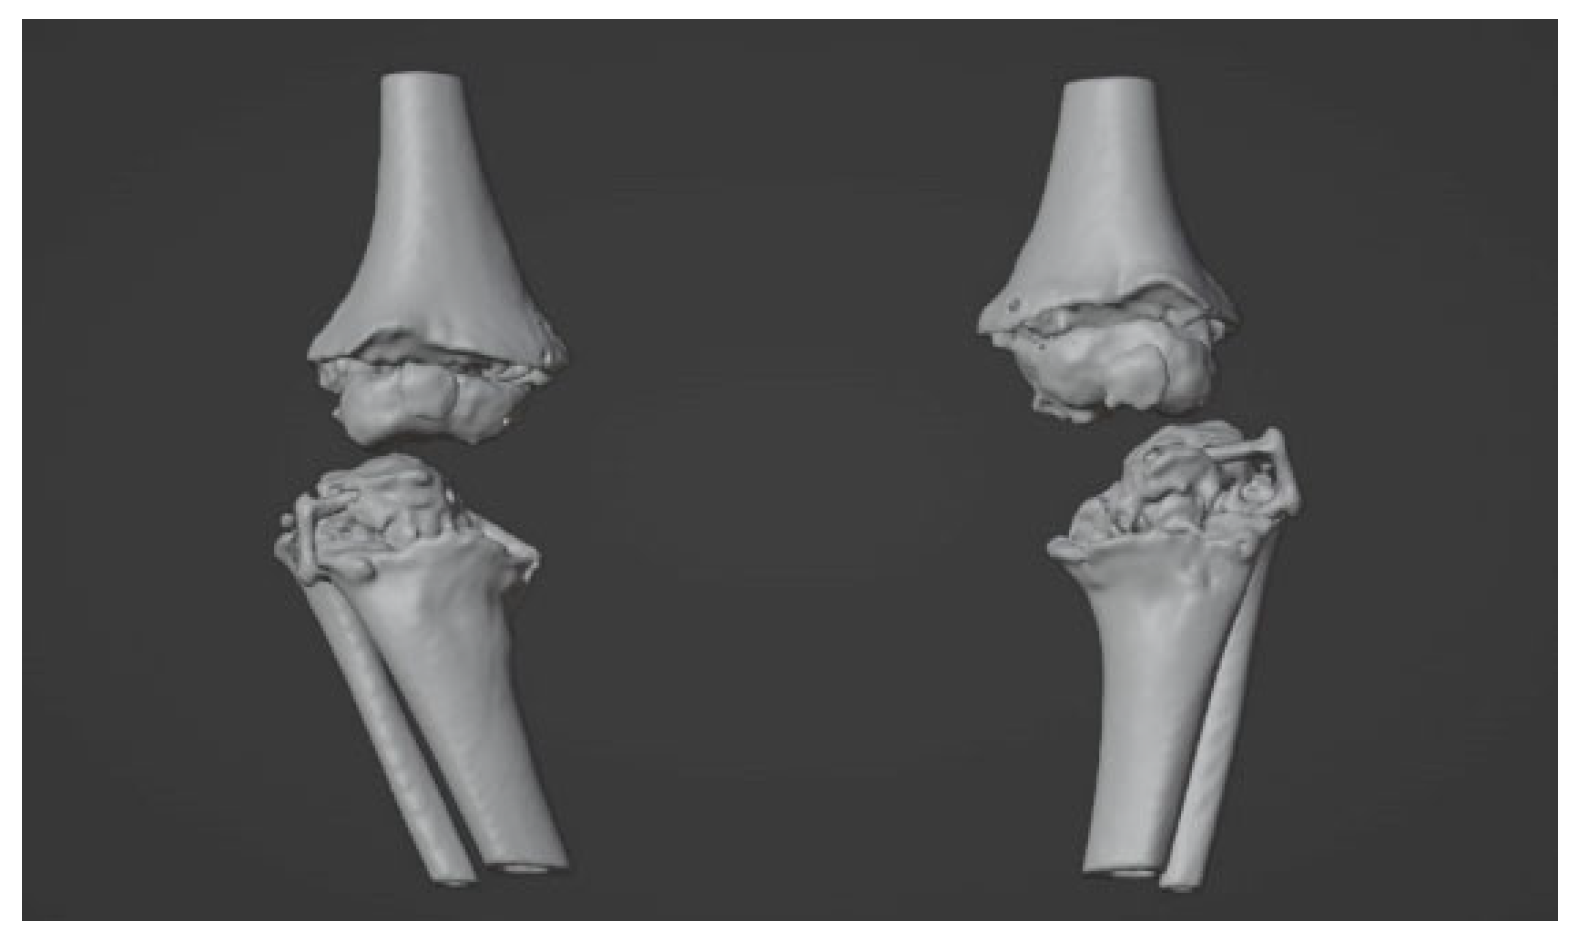

2.2. Image Acquisition and Reconstruction of 3D Model

2.3. Surgical Simulation and Planning